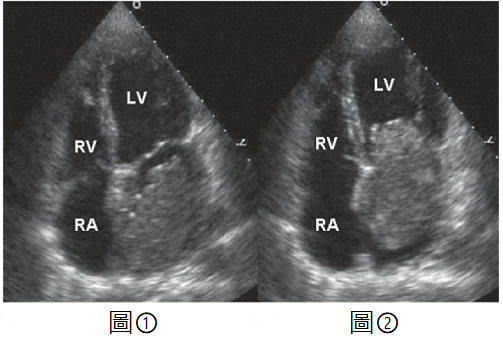

【113-1 醫學(三) 第9題】一位40歲男性病患,沒有任何心臟的病史,因為中風而住院。經詢問病史,過去一年躺臥呈某特定姿勢時,會伴隨眼前發黑的徵兆(black out)、倦怠、體重減輕等狀況;身體診察發現心臟聽診於心尖部舒張中期有一低頻心音,輕微杵狀指(digital clubbing);心臟超音波檢查如附圖。圖①為心室收縮期呈像,圖②為心室舒張期呈像 (RA=右心房;RV=右心室;LV=左心室),經診斷為左心房黏液瘤(left atrial myxoma),下列敘述何者正確?

詳解

破題關鍵

這題的關鍵在於綜合病患的臨床表現(中風、姿勢性眼前發黑、體重減輕、心尖部舒張中期低頻心音、杵狀指)以及心臟超音波影像中左心房內會隨心跳移動的腫塊,這些都強烈指向左心房黏液瘤。影像中腫塊在舒張期(圖②)明顯突出至左心室,造成血流阻塞,是診斷的決定性線索。